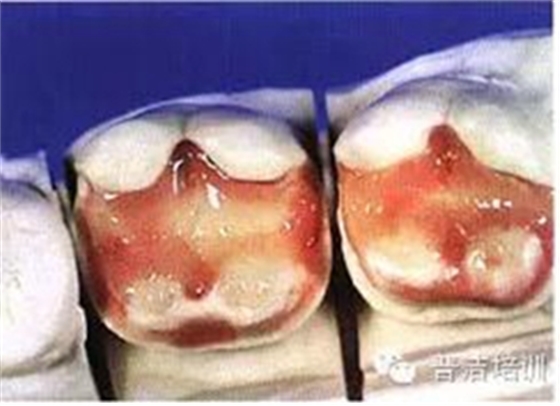

十六、最終的修復(fù)體,是不是很漂亮

修復(fù)后一周復(fù)查